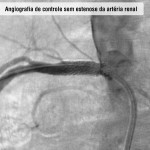

Estenose da artéria renal

O que é

Estreitamentos das artérias dos rins – levam sangue e ajudam os rins a filtrar o sangue e também a controlar a pressão arterial por auxiliar a secretar o hormônio renina – que impedem o órgão de trabalhar corretamente.

Diagnóstico

É feito com base no exame clínico e em exames complementares como ultrassom abdominal (mostra os vasos sanguíneos e o órgão e facilita a localização de coágulos ou áreas de estreitamento e a determinação do tamanho do rim), ecografia vascular com Doppler (analisa precisamente o fluxo sanguíneo renal e estima o grau de estreitamento das artérias renais), angiotomografia computadorizada (revela com precisão a estrutura da parede dos vasos sanguíneos de médio e grosso calibres), angioressonância magnética (produz imagens bi ou tridimensionais das estruturas internas do órgão), angiografia (localiza os estreitamentos ou a obstrução através de raio-x) e cintiolografia renal (analisa o fluxo sanguíneo nos rins).

Tratamento

Inicialmente, o especialista utiliza medicamentos, mas quando o uso é ineficiente, levando à perda da função renal, recomenda-se a angioplastia renal.

Angioplasita renal

Técnica cirúrgica minimamente invasiva indicada, basicamente, para casos de estenoses críticas (acima de 70%) de uma ou de ambas as artérias renais com comprometimento da função dos rins.

Fotos